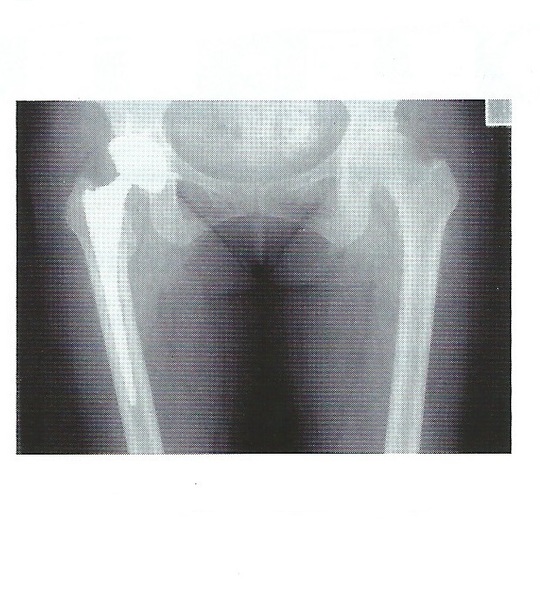

手術

股関節の状態により、寛骨臼あるいは大腿骨の骨切術や、変形が高度な場合には人工関節置換術を行うことがあります。

人工関節全置換術